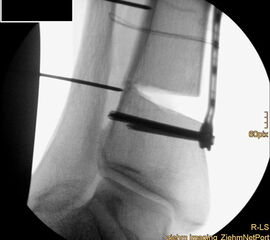

Auch hier wird die Korrektur im CORA (Center oft Rotation and Angulation) durchgeführt. Primär werden intraoperativ unter Bildwandler Kontrolle Kirschner Drähte als Sägelehre konvergierend eingebracht. Dann wird der geplante medialbasige Keil mit der oszillierenden Säge entfernt. Die laterale Kortikalis sollte geschont werden, sie dient als Drehpunkt für die Osteotomie. Die Osteosynthese kann dann im Sinne einer Zuggurtung ein besonders stabiles Konstrukt bilden. Liegen mehrdimensionale Deformitäten vor, die eine Korrektur in Translations- und Rotationsebene erfordern, ist eine Durchtrennung der lateralen Kortikalis notwendig, ebenso bei ausgedehnten Korrekturen mit Keilhöhen über 10mm 218.

Wir benutzen zur Osteosynthese 3,5 mm LCP T-Platten. In der intraoperativen Röntgenkontrolle kann im seitlichen Bild die Zentrierung des Talus überprüft werden, und ggf. durch eine milde extendierende oder flektierende Korrekturkomponente verbessert werden 18. Eine begleitende Deformität der Fibula korrigieren wir üblicherweise mit einer z-förmigen Osteotomie die wir mit einem 1/3 Rohrplättchen sowie einer Zugschraube sichern 18.